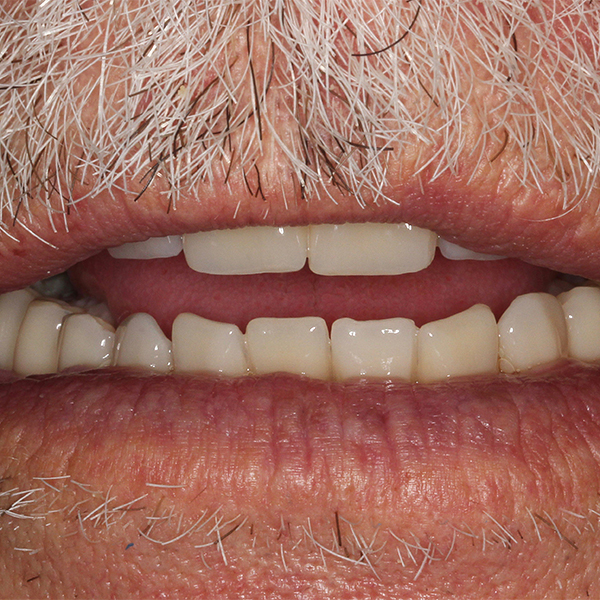

Après la mise en moufle et l'ébouillantage, les dents ont été repositionnées, conditionnées et des caractérisations blanchâtres, pourpres, orange clair, bleues et roses ont d'abord été réalisées au niveau du le bouclier labial. La base a ensuite été incrustée de résines pour prothèses de couleurs orange-rouge, rouge foncé, rouge clair, rose et rose foncé, et tous les polymères à chaud ont été pressés en une seule fois. Après le stockage sous pression, les prothèses finies ont été démouflées, finies et polies. La stratification anatomique tridimensionnelle de VITAPAN EXCELL en masse d'émail, de collet et de dentine avait un aspect absolument naturel dans l'anatomie muco-gingivale reproduite de la base prothétique. Le patient a pu s'habituer rapidement à sa nouvelle prothèse, notamment grâce à l'effet esthétique réussi. Après une courte phase d'adaptation et des corrections minimes dans l'environnement biodynamique, il s'est très bien débrouillé avec sa première restauration prothétique amovible complète et en était pleinement satisfait.